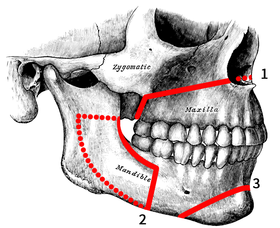

12. Surgery on midface (Lefort 1-2, 3.. Midface lift, high cut lf1)

12. Surgery on midface (Lefort 1-2, 3.. Midface lift, high cut lf1)

22. Orthognatic surgery